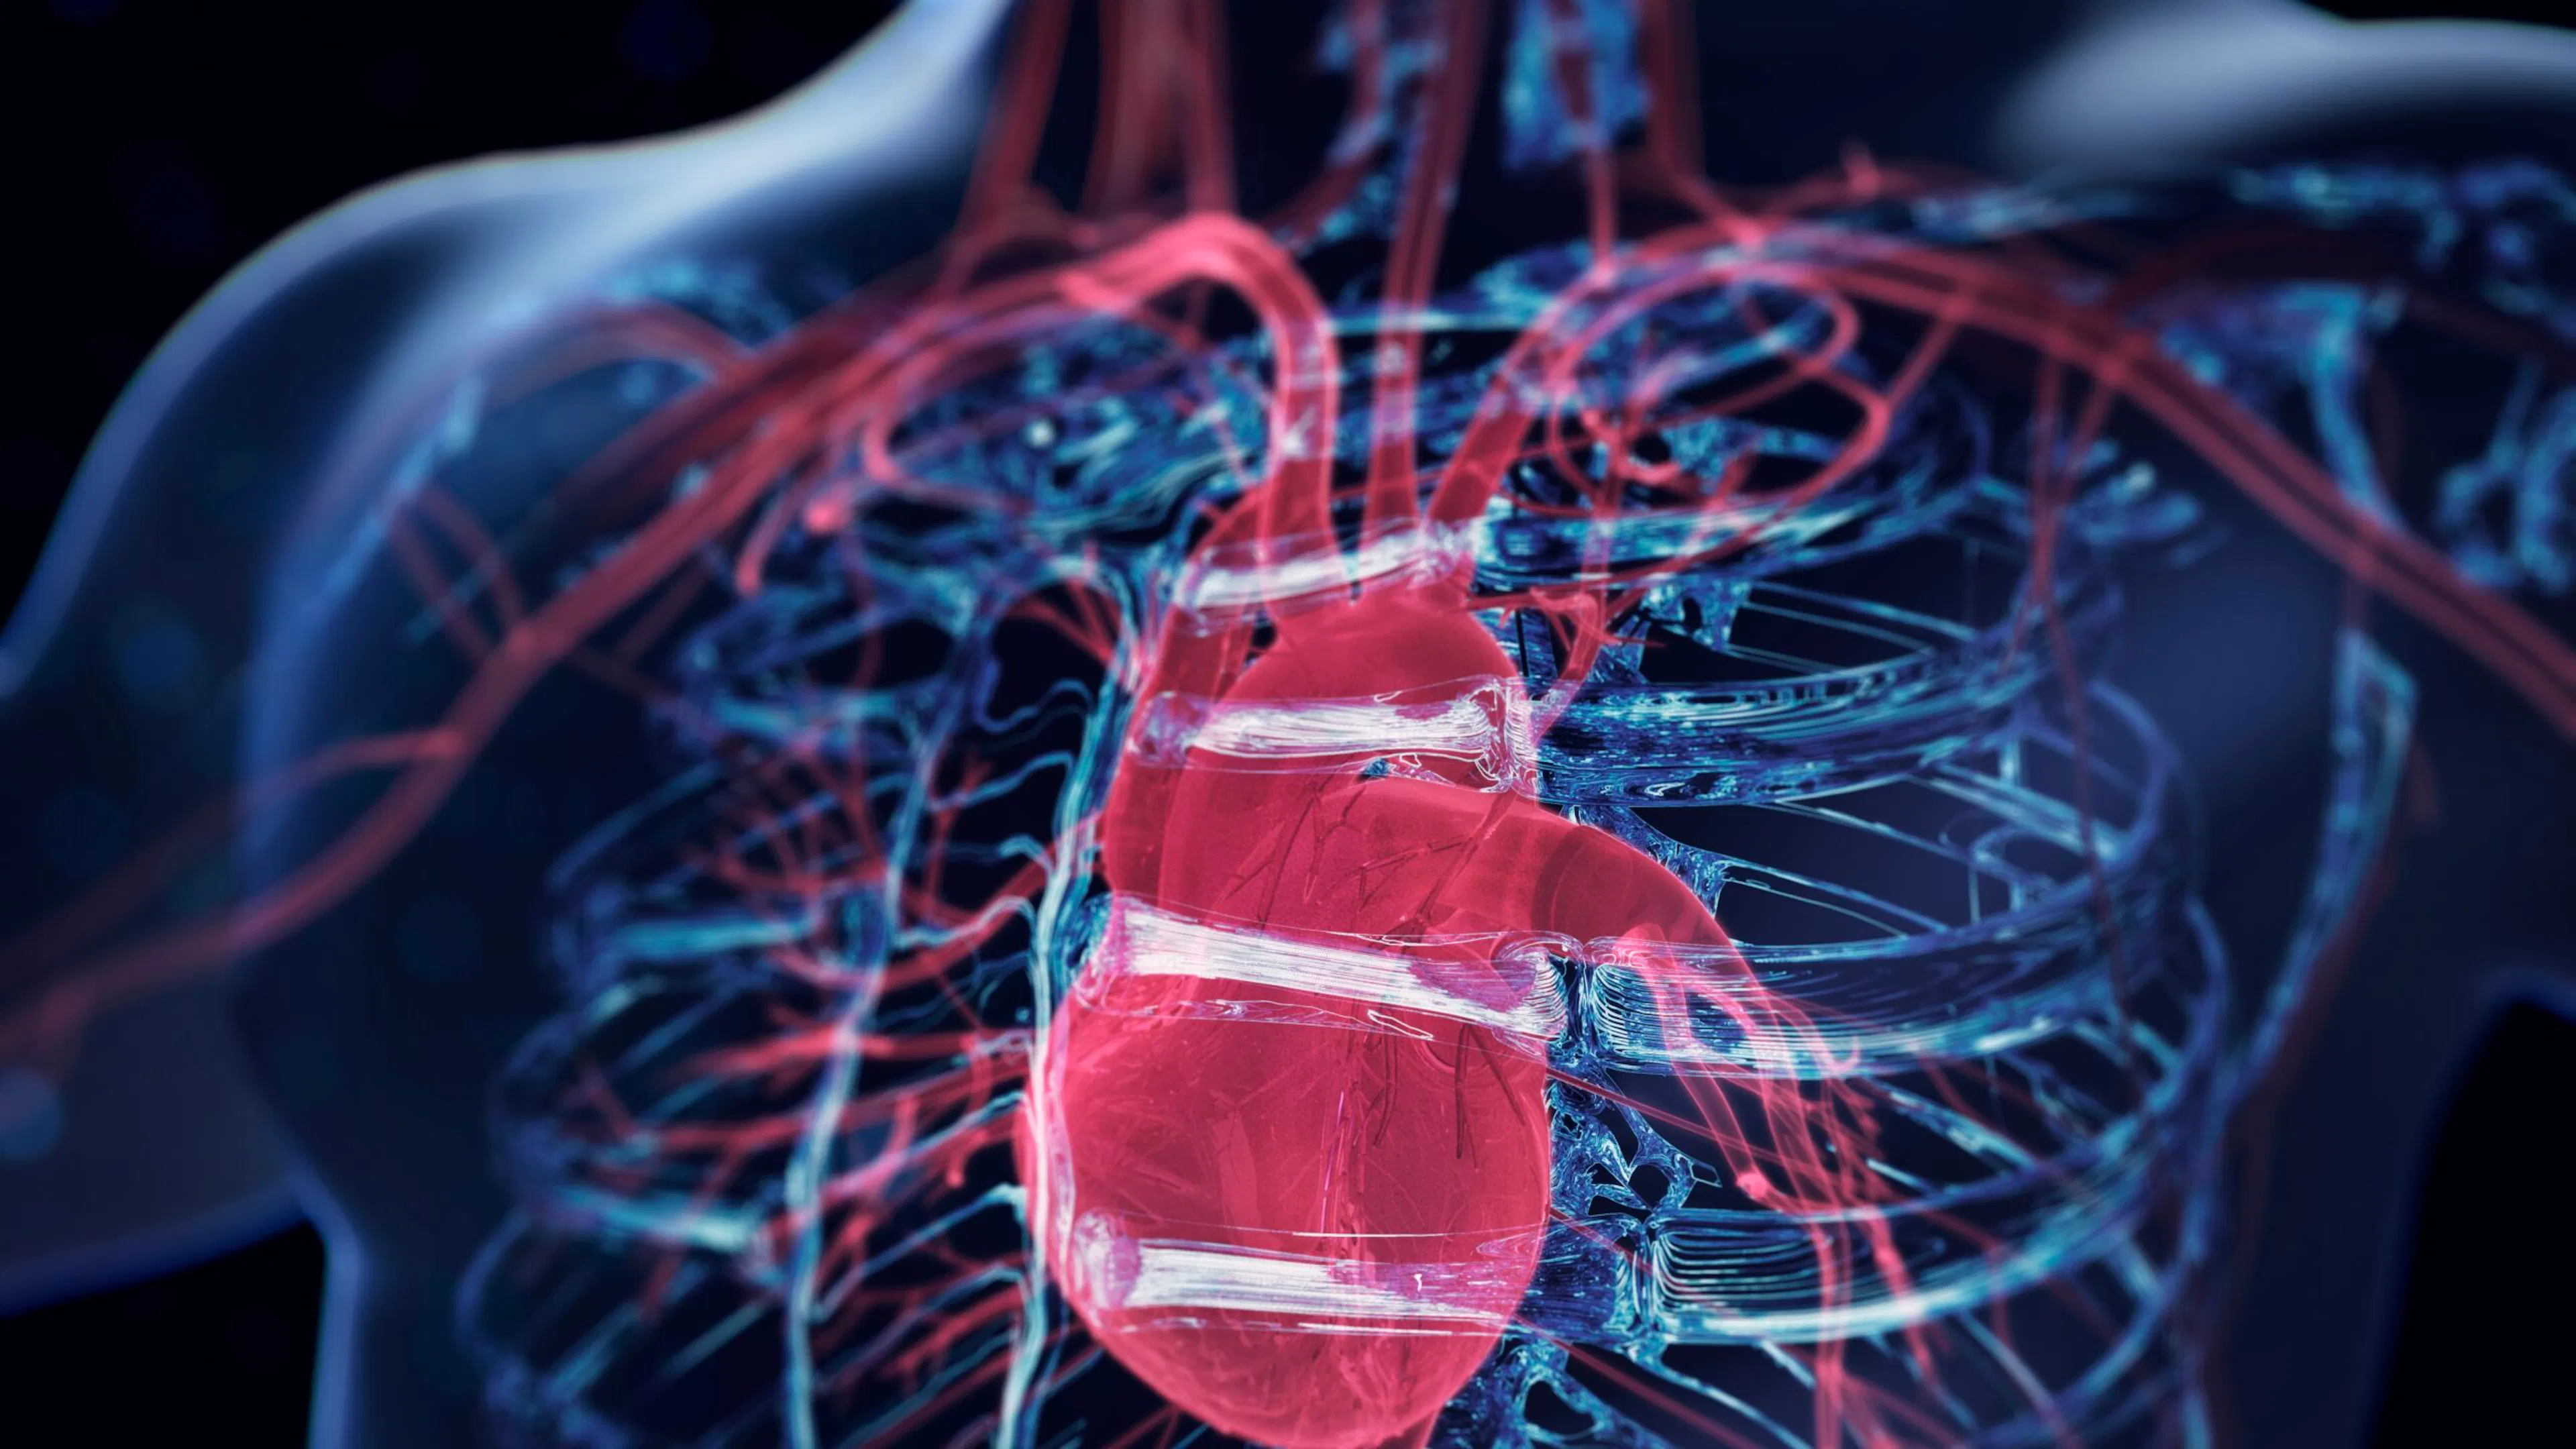

The Enhanced Games And The Billionaire Dream Of Superhumans